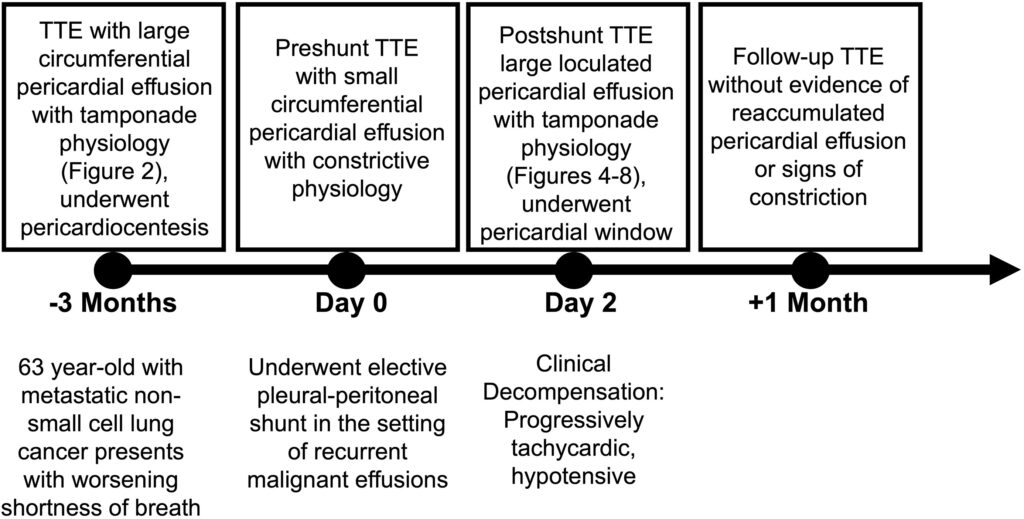

Paciente de 63 anos de idade com neoplasia pulmonar metastática foi admitido para realização de um shunt pleuro-peritoneal em razão de derrame pleural recorrente e passado de múltiplas toracocenteses.

Seu histórico recente incluía um tamponamento cardíaco 03 meses antes em razão de um derrame pericárdico, de etiologia maligna, circunferencial necessitando de pericardiocentese.

À época, o ecocardiograma mostrou um derrame pericárdico circunferencial importante com invaginação (colapso) do AD e um relaxamento ventricular direito retardado sugerindo fisiologia de tamponamento.

O paciente foi submetido a pericardiocentese percutânea com retirada de 500 mL de líquido hemático. A análise histopatológica foi consistente com adenocarcinoma metastático.

Na internação atual para a realização do shunt, a tomografia de tórax mostrou um derrame pleural importante com colapso total do lobo inferior esquerdo do pulmão, bem como documentou a presença de um derrame pericárdico leve a moderado.

Novo ecocardiograma mostrou um pequeno derrame pericárdico circunferencial, medindo 3-6 mm de diâmetro, com variação do influxo mitral exacerbada (31%) e movimento paradoxal do septo interventricular. Achados consistentes com fisiologia restritiva. O VD apresentava diâmetro diastólico no limite superior da normalidade e com função sistólica preservada.

No segundo dia após a realização do shunt, o paciente passou a ficar taquicárdico (FC 115 bpm) e hipotenso (86×56 mmHg). Eletrocardiograma demonstrou taquicardia sinusal e alterações inespecíficas da repolarização ventricular. Já o exame físico documentou turgência jugular patológica, abafamento de bulhas e pulso paradoxal.

Um ecocardiograma foi novamente realizado e um importante derrame pericárdico foi documentado, contudo com aspecto multiloculado resultando em compressão de todas as 4 câmaras cardíacas.

Uma janela pericárdica, por acesso subxifoide, foi realizada com drenagem de 500 mL de líquido hemático turvo, com melhora hemodinâmica imediata do paciente. As adesões pericárdicas, densas, foram manualmente dissecadas.

Após recuperação clínica, o paciente seguiu acompanhamento ambulatorial e o controle ecocardiográfico realizado 30 dias após não demonstrou novo derrame.